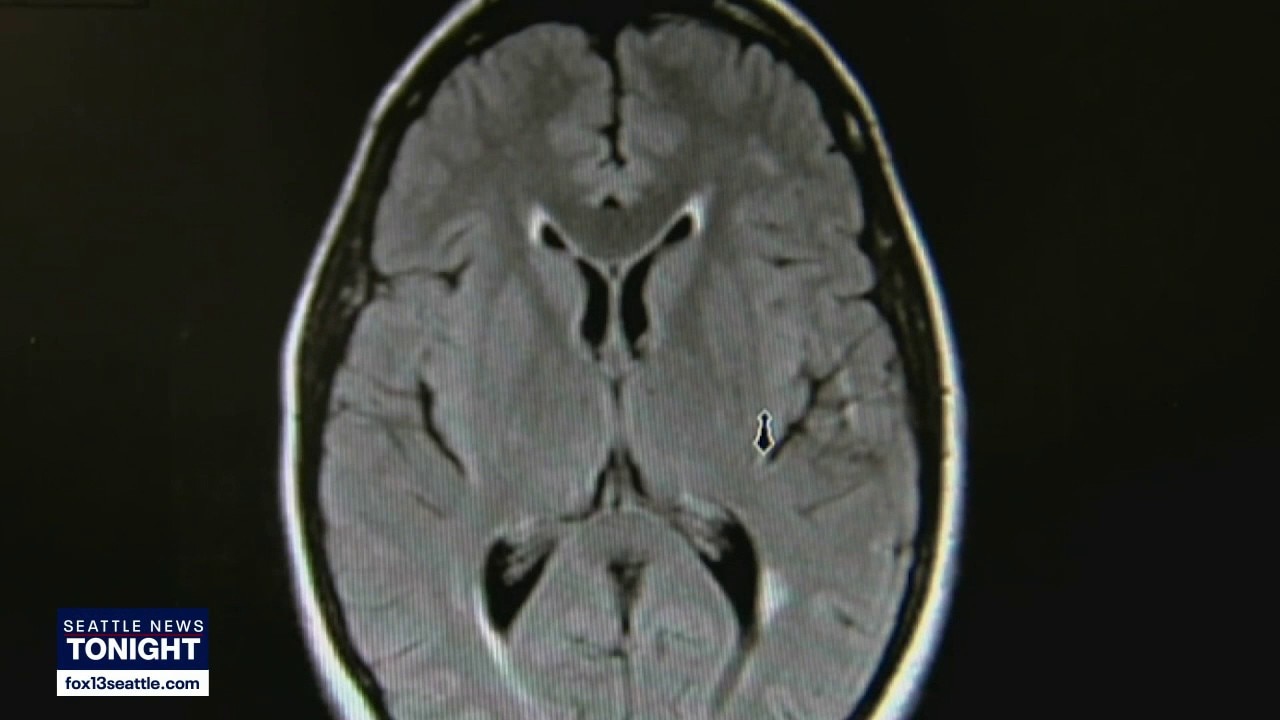

Research shows how movement fights dementia